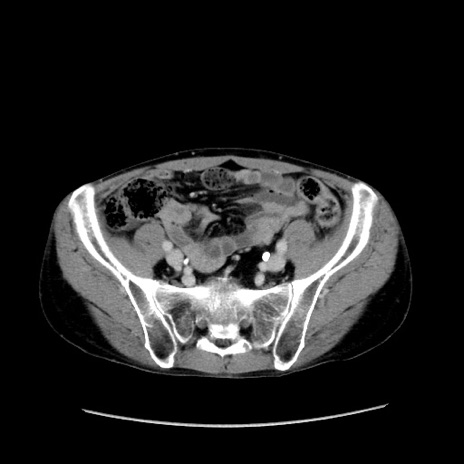

冠状断像